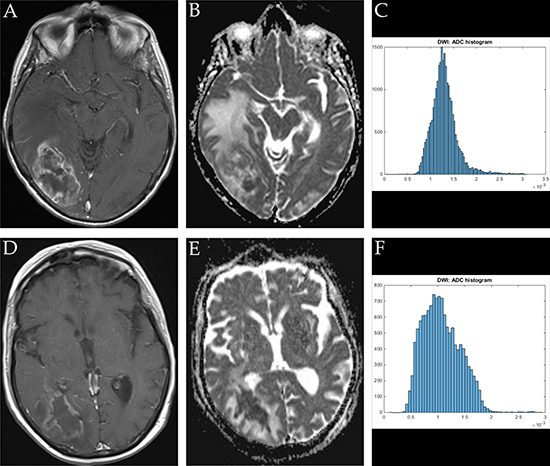

ADC volume histogram analysis gave the following values for the overall collective (each median (range) and mean value ± standard deviation, all in x 10−5 mm2 x s−1): ADCmin = 24.700 (101.20), 27.39 ± 25.94, ADCmean = 120.66 (148.53), 124.36 ± 31.18, ADCmax = 283.70 (290.50), 275.06 ± 55.81, ADCp10 = 77.60 (341.40), 80.89 ± 37.18, ADCp25 = 92.65 (110.60), 93.68 ± 25.40, ADCp75 = 147.50 (200.30), 149.95 ± 42.63, ADCp90 = 172.63 (218.18), 199.36 ± 203.90, ADCmedian = 117.40 (875.20), 127.13 ± 86.37, ADCmodus = 106.30 (282.20), 111.41 ± 51.29. Evaluation of histogram-based characteristics of the investigated volumes for the overall collective gave the following values (each median (range) and mean value ± standard deviation): skewness = 0.581 (5.86), 0.69 ± 0.79, entropy = 4.59 (2.59), 4.49 ± 0.59 and kurtosis = 3.10 (22.19), 4.10 ± 3.27. Figures 1, 2 and 3 provide examples of ADC maps (B, E) coregistered to corresponding T1 weighted post contrast images (A, D) and the respective whole lesion histograms (C, F) of morphologically similar appearing GBM and BA in frequently encountered locations. Table 1 summarizes the findings in the overall collective.

Figure 2: Imaging findings and corresponding ADC-histograms of morphologically resembling temporo-occipital manifestations of GBM and brain abscess. The upper row shows a representative axial T1 weighted post contrast image (A), the corresponding ADC map (B) and the whole lesion ADC-histogram (C) of GBM in a 72 years old female patient. Evaluated parameters were as follows (ADC parameters all in 10-5 mm2 × s-1): ADCmean: 125.20, ADCmin: 41.40, ADCmax: 309.30, ADCp10: 82.20, ADCp25: 99.70, ADCp75 148.90, ADCp90: 163.10, ADCmedian: 125.20, ADCmodus: 150.20, Kurtosis: 4.01, Skewness: 0.51, Entropy: 1.32. The inferior row shows a representative axial T1 weighted post contrast image (D) of brain abscess in a 74 years old female patient, the corresponding axial ADC map (E) and the respective whole lesion ADC-histogram (F). Evaluated parameters were as follows (ADC parameters all in 10-5 mm2 x s-1): ADCmean: 107.22, ADCmin: 10.60, ADCmax: 291.90, ADCp10: 63.95, ADCp25: 80.03, ADCp75: 131.00, ADCp90: 155.60 x, ADCmedian: 103.40, ADCmodus 99.10, Kurtosis: 3.36, Skewness: 0.56, Entropy: 4.75.